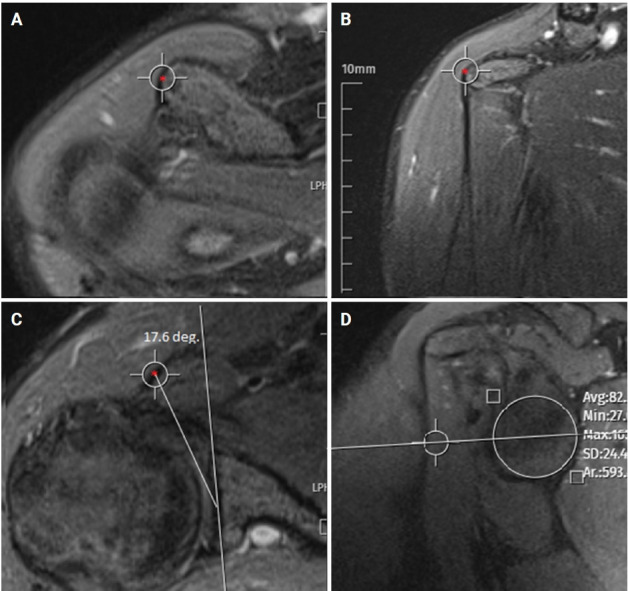

Methods: This study included 72 patients who underwent surgery for ASI and 72 age- and sex-matched controls. The sagittal central glenoid- coracoid angle (scGCA) and axial central glenoid-coracoid angle (acGCA), which assess the coracoid apex position relative to the glenoid center, the glenoid version (GV), and glenoid inclination (GI) were evaluated using magnetic resonance imaging. The critical shoulder angle (CSA) was measured using true anterior-posterior radiographs.

Abstract Image